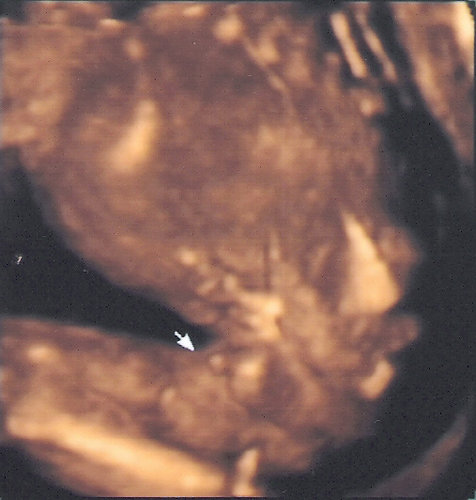

ثانيا : الولد

في الاسبوع ال19